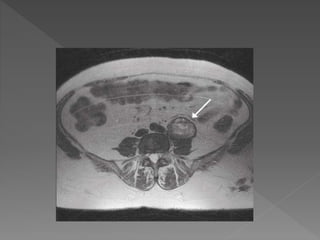

An article inthe Gurdian newspaper UK in March 2013 claimed that “five worst medical” nightmares a Pt faces, three related to surgery: 1. Wrong site surgery 2. Wrong patient surgery 3. Retained instruments and swabs The rate of harm in surgical patient is unknown but probably occur in about 10% surgical patient, though much of this harm will be minor.

1. Wrong patientin the operation theatre. 2. Surgery performed in the wrong side or site 3. Wrong procedure 4. Failure to communicate changes in the patient condition. 5. Disagreement about proceeding. 6. Retained instruments or swabs.